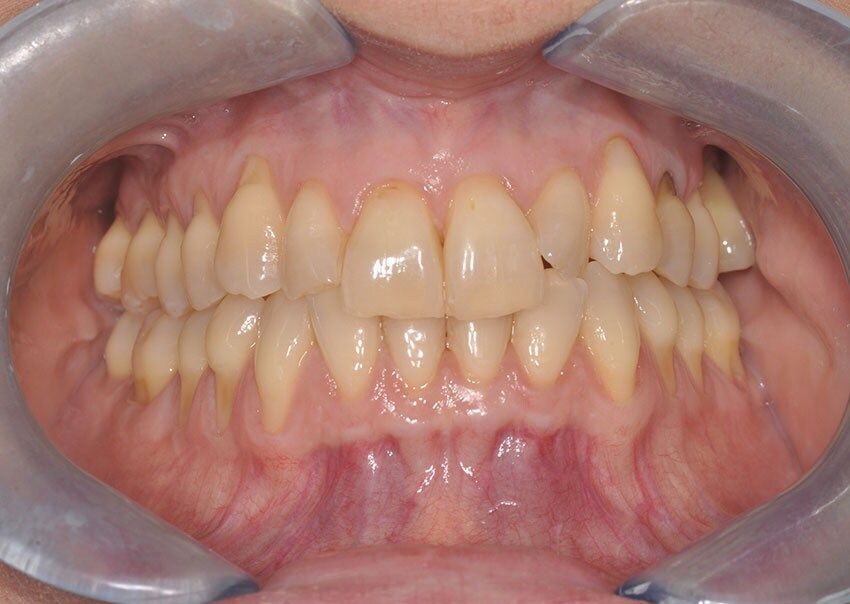

La chirurgia muco gengivale include i trattamenti dedicati alla correzione di recessioni, difetti gengivali e alterazioni estetiche del sorriso. Richiedono una tecnica che funziona nelle mani di pochi, per questo il nostro centro si avvale di uno specialista di fama internazionale, per risultati naturali, che garantiscano il successo atteso e, soprattutto, siano stabili nel tempo.

Tutti gli interventi di chirurgia orale vengono eseguiti in una sala chirurgica dedicata, in presenza di un medico anestesista, con possibilità di ricorrere alla sedazione cosciente, una procedura anestesiologica sicura e controllata che permette al paziente di entrare in uno stato di profondo rilassamento, pur rimanendo sveglio e collaborante, riducendo ansia e stress e garantendo serenità e comfort al paziente durante tutta la procedura.